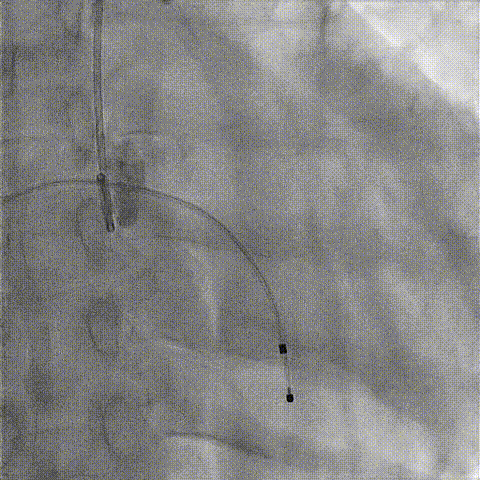

根部造影

球囊预扩

释放工作位造影